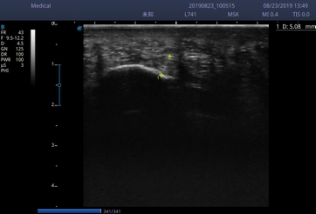

女士足跟部压痛明显,双侧足弓塌陷(图 4),足底压力测试发现足扁平(图 5),接着进行了足底超声检查,提示左侧足底筋膜厚度较右侧明显增厚(图6,7)。康复医生给予明确的诊断足底筋膜炎炎。

李女士平素工作繁忙,没有足够的时间来医院做物理治疗,所以选择了可视化超声引导下药物注射的治疗方法(图8),注射后1周VAS评分从8分下降至2分,之后配合康复锻炼,同时配置了足底矫形鞋垫(图9),1月后足跟疼痛完全消失。

图7:左侧足底筋膜厚度5.08mm

图8:右侧足底筋膜厚度2.13mm